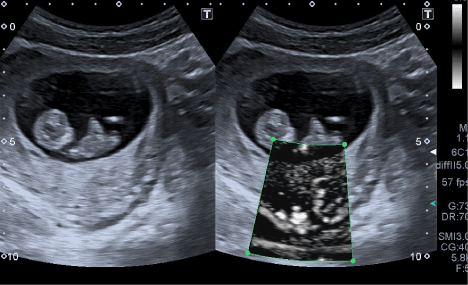

When examining the intraplacental vascular bed with patients possessing normal levels of the progesterone content (Figure 1), the homogeneous placental tissue is visualized, which is characterized by the distinct adequate vascular network and active blood flow.

Figure 1. Normal placenta version. Left: B-mode, right – SMI